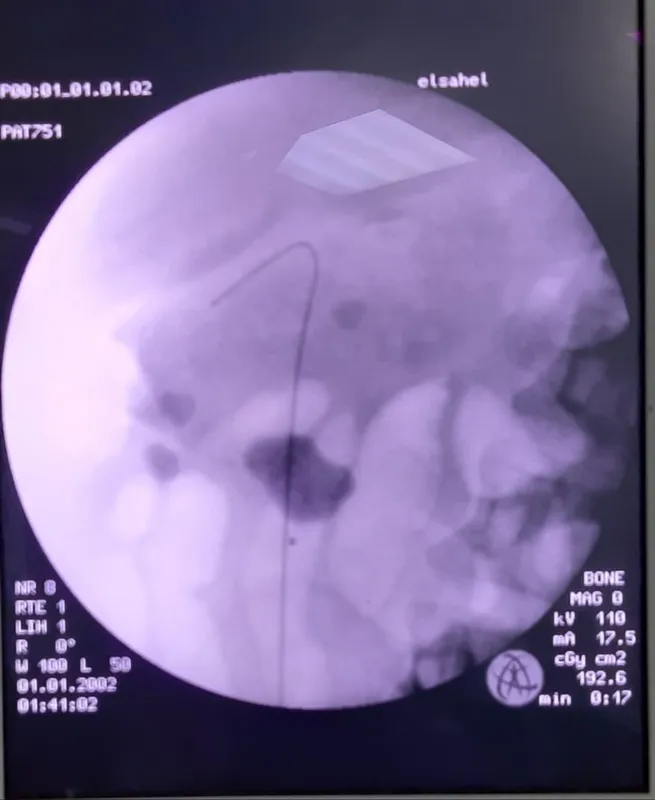

وأضاف أنه من هذا المنطلق تم اليوم خروج أصغر مصاب بفيروس كورونا المستجد من مستشفى الساحل التعليمي ويبلغ من العمر 22 يوم كما تم إجراء تدخل جراحى عاجل لإنقاذ حياة أحد المرضى وقام فريق طبى متميز من أبطال المستشفى بعمل منظار جراحي وتركيب دعامتين بالحالبين لمريض فشل كلوى مصاب بفيروس كورونا (كوفيد-19) لإنقاذ حياته.

وأضاف أن المريض الآخر تم حجزه بالمستشفى جراء إصابته بفيروس كورونا المستجد بالإضافة إلى أنه يعاني من فشل كلوي حاد نتيجة لإنسداد حوض الكليتين بحصوات متشعبة مما استدعى ضرورة التدخل الجراحى العاجل وعمل منظار جراحى وتركيب دعامتين بالحالبين لإنقاذ حياة المريض، إلى ان استقرت حالته ويخضع حاليا للملاحظة على مدار الساعة.